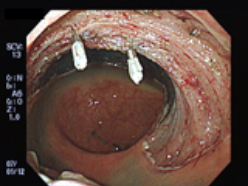

早期大腸癌に対するESD

3.病変を取り去った後の直腸と切除標本。病変部の大きさはφ8cmでした。